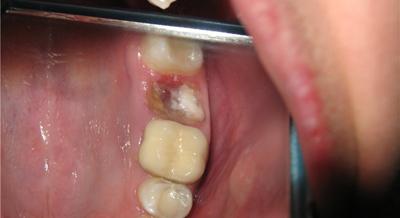

Альвеолит — воспаление стенок лунки — развивается часто после травматично проведенной операции, снижающей защитные свойства тканей. Его возникновению способствуют проталкивание в лунку во время операции зубных отложений или содержимого кариозной полости зуба; наличие оставшейся в ней патологической ткани, осколков кости и зуба;

длительное кровотечение из раны; отсутствие в лунке кровяного сгустка или механическое разрушение его; нарушение больным послеоперационного режима и плохой уход за полостью рта. Причиной альвеолита может стать инфекция, находящаяся в лунке, когда зуб удаляют по поводу острого и обострившегося хронического периодонтита или осложненного пародонтита.

Клиническая картина. В начальной стадии альвеолита появляется непостоянная ноющая боль в лунке, которая усиливается во время еды. Общее состояние больного не нарушается, температура тела нормальная. Лунка зуба только частично выполнена рыхлым, распадающимся сгустком крови. В некоторых случаях сгусток в ней совсем отсутствует.

В лунке имеются остатки пищи, слюна, стенки ее обнажены. Слизистая оболочка края десны красного цвета, прикосновение к ней в этом месте болезненно. При дальнейшем развитии воспалительного процесса боль усиливается, становится постоянной, ир-радиирует в ухо, висок, соответствующую половину головы. Ухудшается общее состояние больного, появляются недомогание, субфебрильная температура тела.

Прием пищи из-за боли затруднен. В лунке зуба содержатся остатки распавшегося сгустка крови, стенки ее покрыты серым налетом с неприятным гнилостным запахом. Слизистая оболочка вокруг лунки гиперемирована, отечна, болезненна при пальпации. Поднижнечелюстные лимфатические узлы увеличены, болезненны.